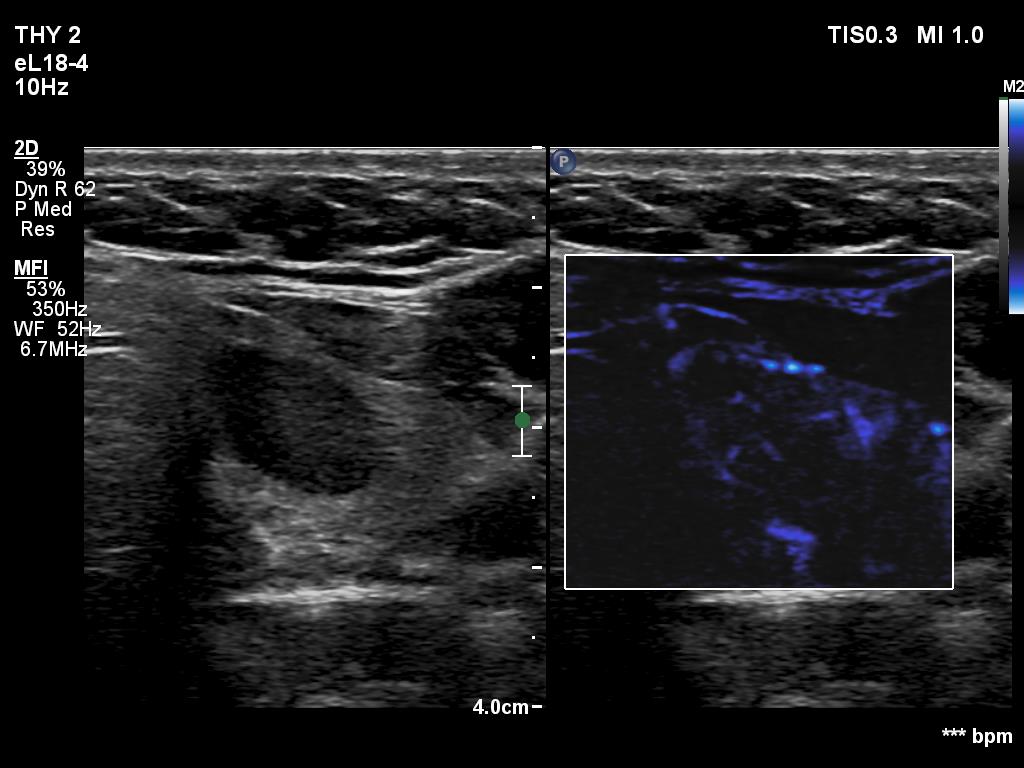

Left lobe, transverse scan, microflow imaging. The distribution of vessels is regular.